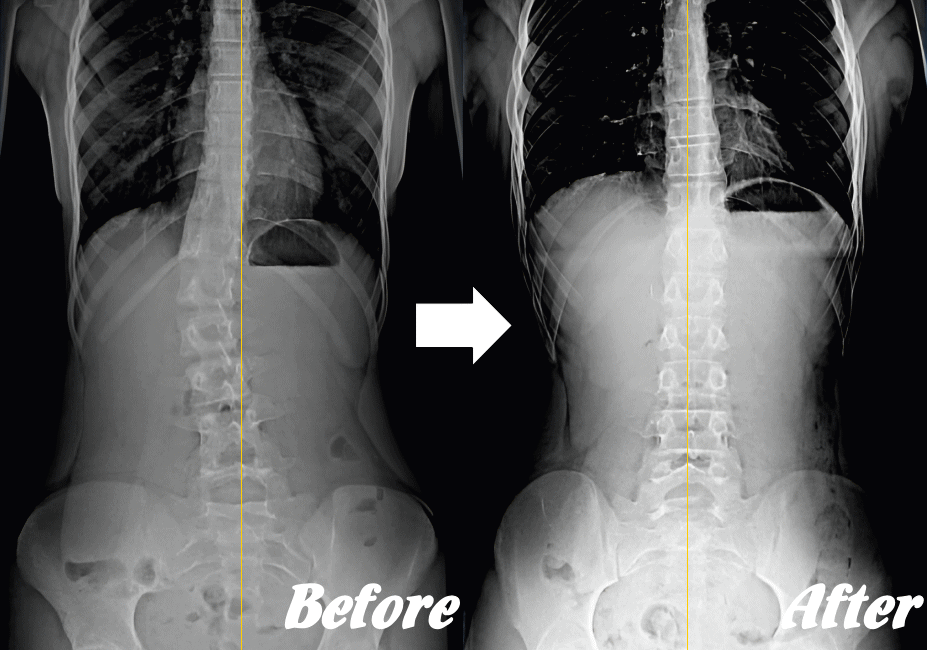

【体の整体】による変化

※ X線/MRI/CT検査画像のデータをお持ちの方はご持参いただければ当院で参考にさせていただきます。